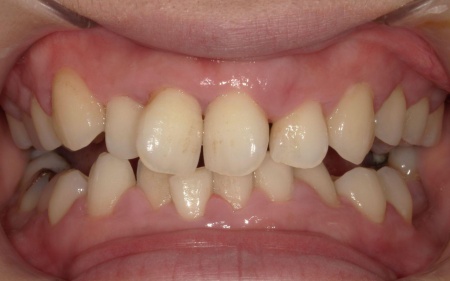

10代女性 乱れた歯並びと噛み合わせをワイヤー矯正で改善した症例

- 矯正歯科

- ワイヤー矯正

- 治療期間の目安 1年6ヶ月

- 治療費総額の目安 770,000円

・治療中、発音しにくい場合があります ・治療中、舌が動かしにくいことがあります ・治療中、装置によってまれに頬の内側が傷つき、口内炎になる場合があります ・歯の移動に伴って、違和感や痛みを感じる場合があります ・冷たいものを飲んだときに歯がしみる「知覚過敏」の症状が出る場合があります ・正...